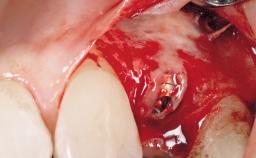

Early Placement of an Implant in a Maxillary Right Central Incisor Site

This 41-year-old female patient was referred to the clinic for the replacement of the right central incisor, since the tooth had developed a root fracture in the long axis that made extraction necessary. The healthy, non-smoking patient was first seen with the tooth still in place. A detailed Esthetic Risk Assessment was performed.The patient was worried about her dental esthetics and had high expectations for a successful treatment outcome from an esthetic point of view. The patient had a medium lip line that displayed parts of the gingiva in the anterior maxilla upon smile.